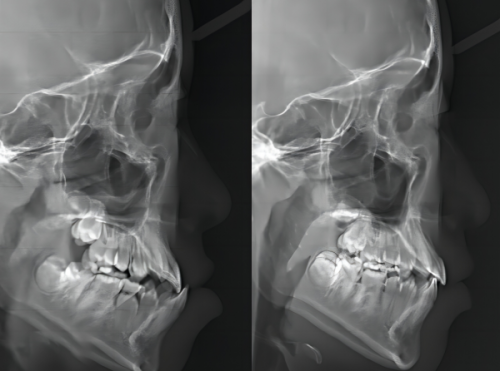

1. 根管预备这是根管治疗的起始关键环节,也是清除感染的第一步。治疗前医生会先拍摄口腔X线片,精细明确髓室的位置、根管的数目和复杂形态,避免在治疗中出现根管遗漏的情况。随后会使用牙科手机打开牙冠,去除已经坏死或感染的牙髓组织,再用一系列专精的根管器械逐步清理、扩大并塑型根管,完全刮除根管内壁附着的感染坏死物质,更终形成一个流畅、规则的根管通路,为后续的消毒和充填操作创造有利条件。这一步通常会在第一次就诊时完成,如果牙齿处于急性炎症期,医生可能会精良行引流减压处理,待炎症缓解后再进行根管预备。

术前评估其实这是根管治疗的前置准备步骤,特别多患者会把它和第一次治疗合并进行。医生会通过拍摄口腔X线片,必要时使用CBCT三维影像检查,全方面了解牙齿的龋坏范围、根尖周炎症的重度程度、根管的弯曲程度和数目等信息,然后根据这些详细情况为你制定个性化的治疗方案,比如是否需要精良行抗炎处理、是否需要在后续添加根管打桩步骤、选择哪种牙冠材料等,确保治疗的针对性和有效性。